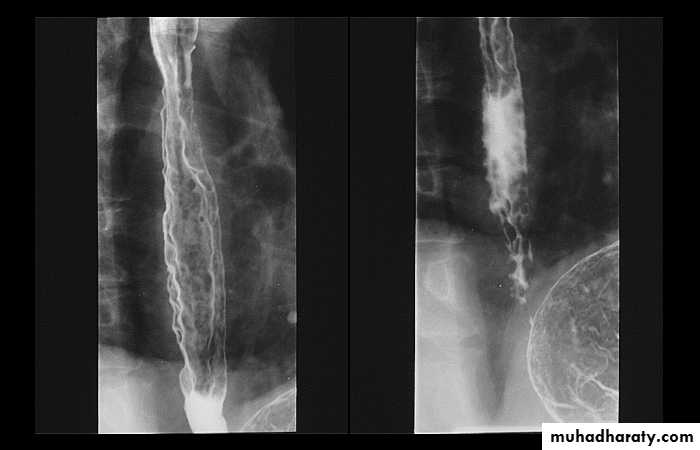

Esophageal Varieces

Dilatation of venous plexus in the wall of the esophagus due to increased pressure ( portal H.T.).Important cause of Hematemesis .

Early changes seen in the mucosa (D.C.) loss of parallelism with thick and tortuous folds.

Later multiple small filling defects (fine cobble stone).

In advanced stage large filling defects ( coarse cobble stone ) .

7More advanced stage elongated and worm like filling defect .

The changes are seen at lower third and gastric fundus.